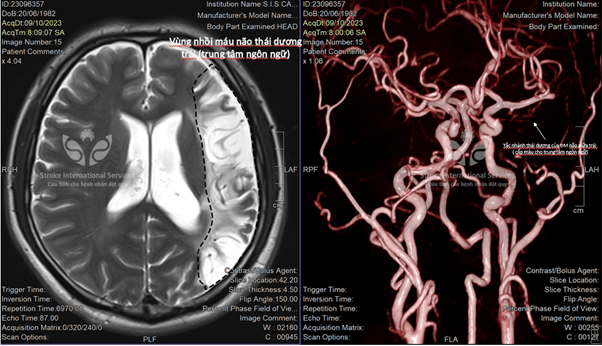

Anh Đ.T.A., sinh năm 1982 tại Thái Nguyên, đã trải qua đột quỵ cách đây 6 năm, sự thiếu may mắn của anh khi không được cấp cứu kịp thời đã qua giờ vàng, dẫn đến di chứng tổn thương não trái gây nói khó.

TS.BS Trần Chí Cường chia sẻ: “Đây là trường hợp đột quỵ khá hiếm gặp! Bệnh nhân không bị yếu liệt mà chỉ bị ảnh hưởng đến chức năng ngôn ngữ: nói khó, viết khó, đôi khi không hiểu và không thể diễn đạt. Vị trí tổn thương trên não thường là thùy thái dương bên trái (trung tâm ngôn ngữ) với người thuận tay phải. Dạng đột quỵ này rất dễ bị bỏ sót và điều trị muộn màng vì triệu chứng thường nhẹ và diễn tiến từ từ. Tuy nhiên, nếu mức độ nặng có thể gây mất ngôn ngữ hoàn toàn ảnh hưởng nhiều đến chất lượng cuộc sống”